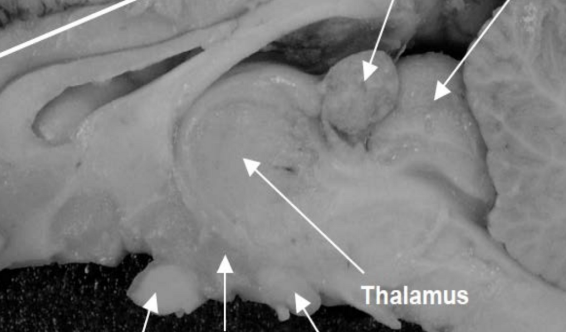

Hypothalamus

Motivation + the 4 Fs (feeding, fleeing, fighting, fornicating)

Mammillary bodies

A

Memories